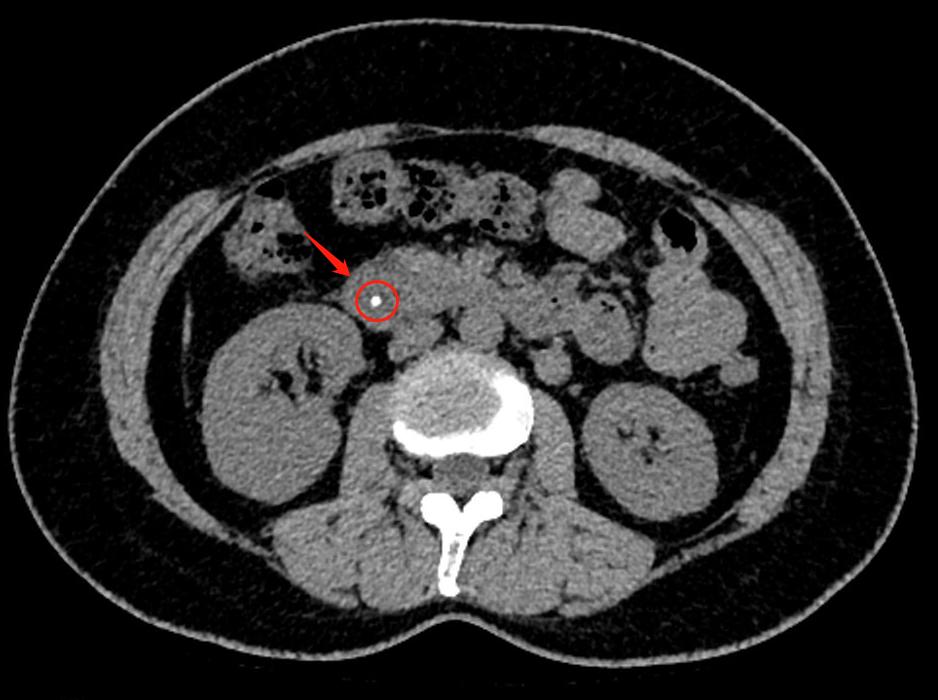

经过了CT检查,很快就找出了原因——胆总管卡着一颗大小约4mm的“石头”。这个石头卡在胆汁与胰液的出口处,让程女士出现腹痛。

程女士的CT片子

医生表示,若再不进行治疗可能会出现进一步发展到重症胰腺炎,会有死亡的风险。